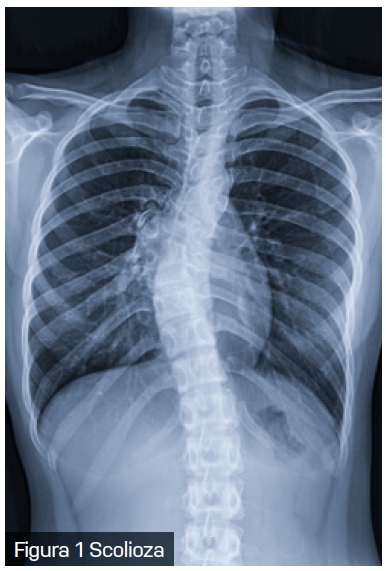

Scolioza, o deformare tridimensională a coloanei vertebrale, este o afecțiune care nu afectează doar aspectul fizic al pacientului, ci poate avea implicații semnificative și asupra sănătății respiratorii. Scolioza are o prevalență variabilă între 0,3% și 15,3% în populația generală.

Modificările structurale cauzate de scolioză au un impact direct asupra mecanicii respiratorii. Deformarea coloanei vertebrale și a toracelui reduce complianța peretelui toracic, limitează mobilitatea coastelor și afectează forța musculaturii intercostale. Aceste schimbări conduc la o scădere a volumului pulmonar și determină compresia focală a căilor respiratorii. În special la copiii cu scolioză cu debut precoce, limitarea creșterii normale a toracelui și a plămânilor poate avea consecințe pe termen lung asupra dezvoltării respiratorii.

În practica clinică, pacienții cu scolioză pot dezvolta un tipar de respirație rapidă și superficială, în încercarea de a compensa rigiditatea peretelui toracic. Această adaptare conduce la o scădere a capacității de efort și la apariția dispneei de efort, una dintre primele manifestări clinice ale scoliozei. Implicarea coloanei toracice (singură sau în combinație cu segmentul lombar) în scolioză este responsabilă pentru complicațiile respiratorii și cardiovasculare, iar distorsiunea cutiei toracice crește efortul respirator necesar.

Datorită interconexiunilor complexe dintre coloana vertebrală, stern și coaste, mișcarea și rotația vertebrelor în cazul scoliozei au un impact semnificativ asupra formei toracelui, generând o latură convexă și una concavă. Pe lângă severitatea curbei coloanei vertebrale, vârsta pacientului joacă un rol în distribuția inegală a gazelor alveolare. Reducerea capacității de a efectua efort fizic la copiii cu scolioză nu se datorează doar scăderii capacității respiratorii, ci și diminuării abilității inimii de a se adapta la cerințele metabolice crescute. De asemenea, micșorarea diametrului anteroposterior al toracelui la acești copii determină o deplasare a inimii, afectând astfel funcționarea acesteia.